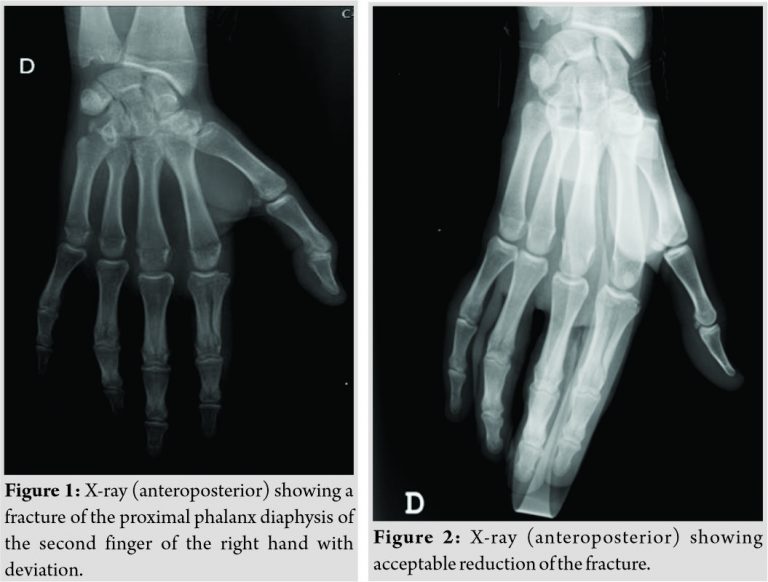

A 15-year-old Caucasian boy with no relevant medical history went to the emergency department after suffering trauma in his right hand caused by a fall forward while playing football. He presented a deformity at the base of the second finger, swelling, and painfully restricted motion. Rotational deformity of the second finger associated with radial deviation and hyperextension was found during physical examination, but neurovascular structures were intact. The X-ray (Fig. 1) showed fracture of the proximal phalanx diaphysis of the second finger of the right hand with deviation. Closed reduction under sedation was performed applying traction and ulnar deviation followed by syndactyly and immobilization with Zimmer splint.